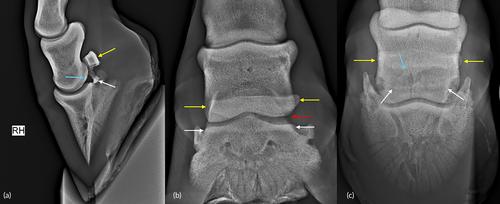

一只2.5岁的温血母马表现为急性发作的严重右后肢跛行和骹骨区域肿胀,持续2周。x线检查显示舟骨横向(水平)移位骨折和远端指间关节半脱位。计算机断层扫描(CT)检查,包括DIP关节造影术,在DIP关节的足底囊中发现了进一步的碎片,并显示DIP关节和舟状囊之间没有通信。六个月后,这匹马在小跑时只表现出轻微的跛行。计算机断层扫描显示大的近端和远端碎片之间部分骨愈合。受伤十个月后,这匹母马已经长得很健康,而且已经有了小马驹。

A 2.5-year-old Warmblood filly presented with an acute onset of severe right hindlimb lameness and pastern region swelling of 2 weeks' duration. Radiographic examination revealed a transverse (horizontal) displaced fracture of the navicular bone and subluxation of the distal interphalangeal (DIP) joint. Computed tomographic (CT) examination, including DIP joint contrast arthrography, identified a further fragment in the plantar pouch of the DIP joint and revealed no communication between the DIP joint and the navicular bursa. Six months later the horse showed only mild lameness at trot. Computed tomographic examination revealed a partial osseous union between the large proximal and distal fragments. Ten months following the injury the mare was pasture sound and in foal.